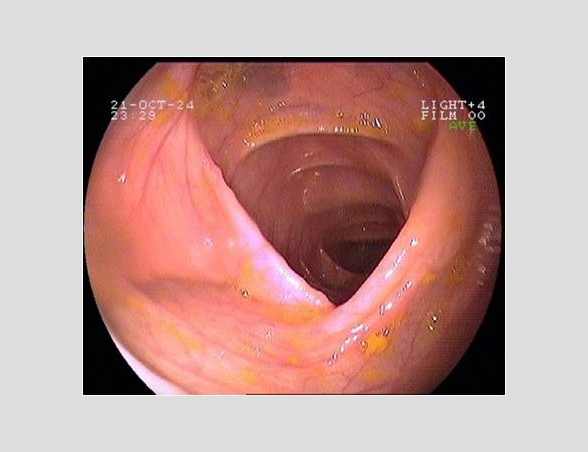

Imágenes tomadas durante la endoscopia digestiva alta y la colonoscopia. Se aprecia una mucosa de aspecto y vascularización normal, sin lesiones visibles. Se progresa con el colonoscopio hasta el íleon. Todo resulta macroscópicamente normal. Se toman biopsias de todos los segmentos explorados.

La endoscopia es el método de elección para el diagnóstico y seguimiento de la EII. Permite una visión macroscópica de la mucosa intestinal y la toma de múltiples biopsias para el estudio histológico.

Realizamos una endoscopia digestiva alta y una colonoscopia a la paciente con toma de biopsias, obteniendo el informe de Anatomía patológica.